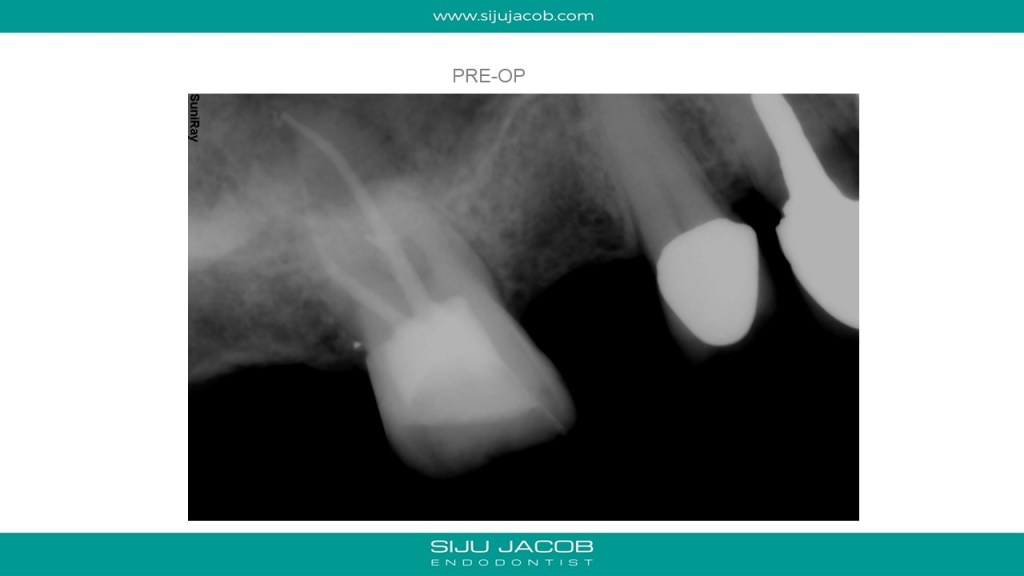

Here’s a trick i use to prevent the MTA from slipping into the canal when the perforation is very close to the canal. This maxillary first molar had a missed Mesio-buccal canal with a perforation. After locating the mesio-buccal canal and cleaning it, the canal was filled with calcium hydroxide. A gutta percha cone was then placed into the canal and sheared off at the coronal level. The perforation was sealed with MTA, a moist cotton pellet was placed in the pulp chamber and the access closed with GIC. After 1 week, the temporary filling is removed and the MTA checked for hardening. The gutta percha placed in the MB canal is then removed with a rotary ni-ti file. The calcium hydroxide placed in the canal is removed and the canal is obturated with gutta percha. A composite core is placed.